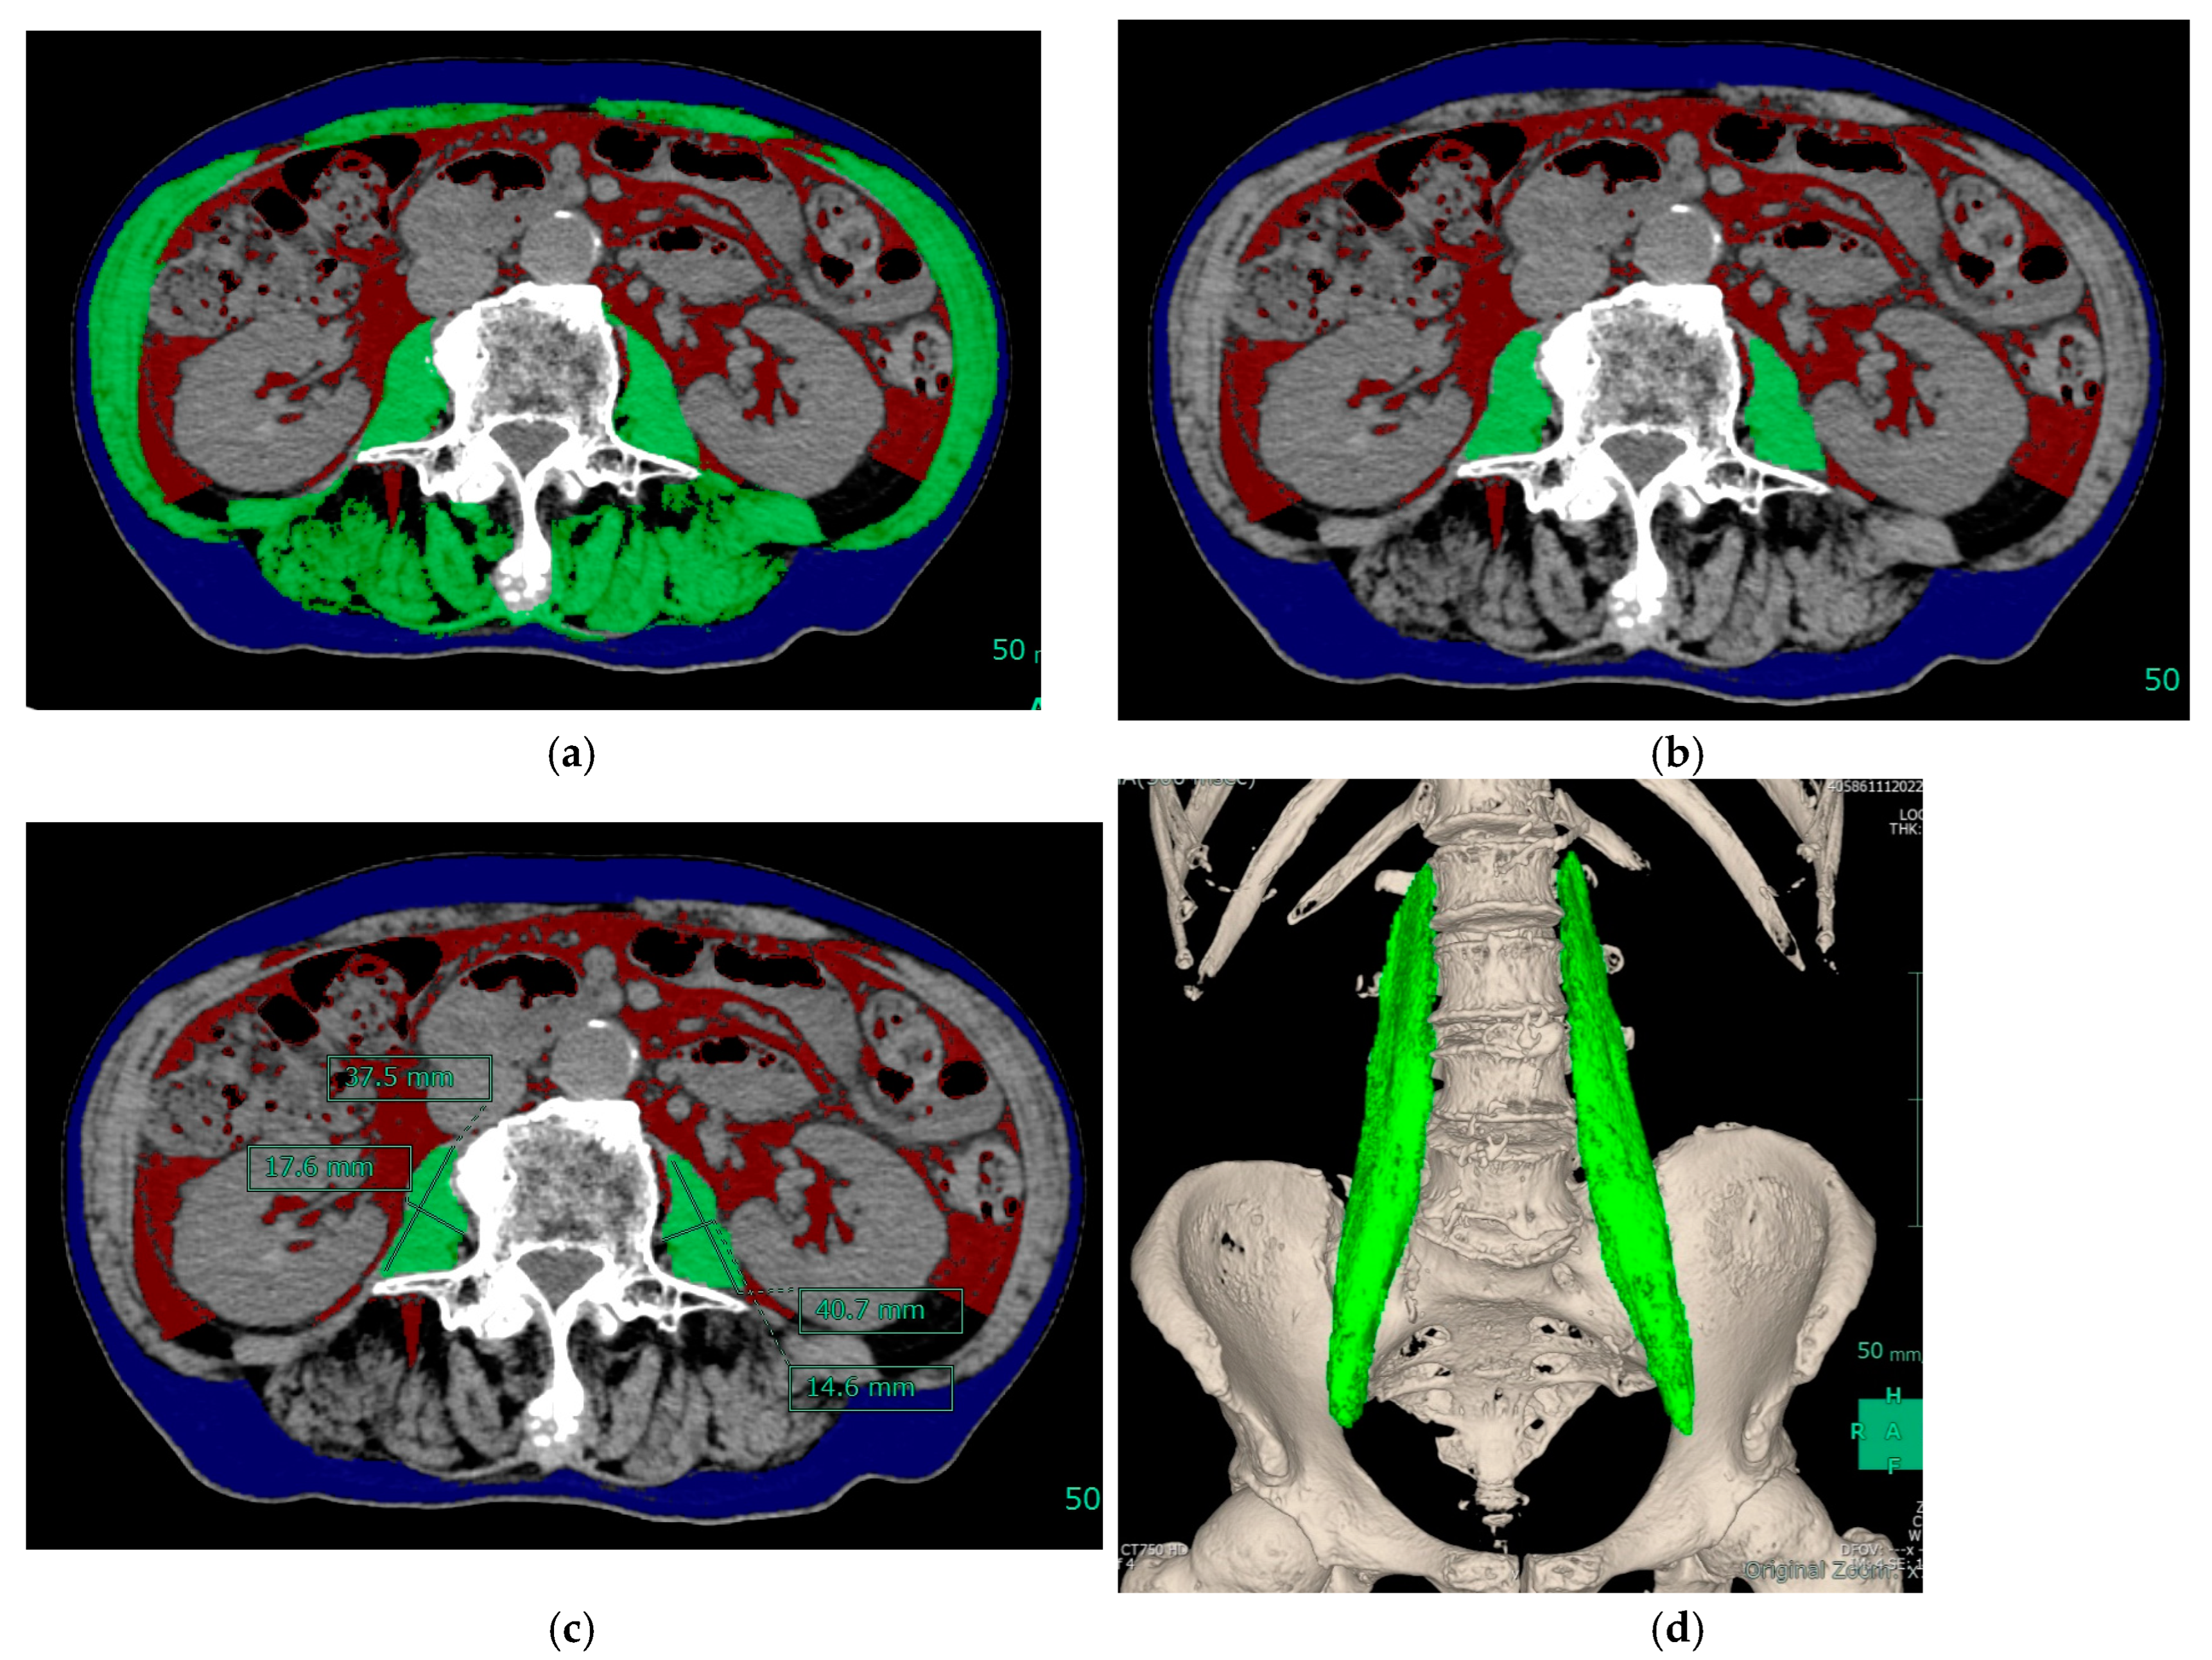

- Ohshima, S. Volume analyzer SYNAPSE VINCENT for liver analysis. J. Hepatobiliary Pancreat. Sci. 2014, 21, 235–238. [Google Scholar] [CrossRef]

- Ogawa, C.; Minami, Y.; Morita, M.; Noda, T.; Arasawa, S.; Izuta, M.; Kubo, A.; Matsunaka, T.; Tamaki, H.; Shibatoge, M.; et al. Prediction of Embolization Area after Conventional Transcatheter Arterial Chemoembolization for Hepatocellular Carcinoma Using SYNAPSE VINCENT. Dig. Dis. 2016, 34, 696–701. [Google Scholar] [CrossRef] [PubMed]

- Ogawa, C.; Minami, Y.; Noda, T.; Arasawa, S.; Izuta, M.; Kubo, A.; Matsunaka, T.; Tamaki, H.; Shibatoge, M.; Kudo, M. Initial Experience Performing Percutaneous Ultrasound Examination with Real-Time Virtual Sonography with Color Display. Oncology 2015, 89 (Suppl. S2), 11–18. [Google Scholar] [CrossRef]